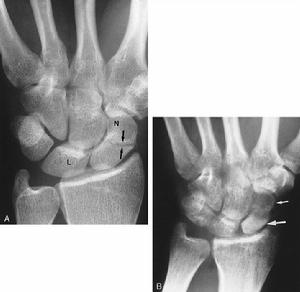

3、X線檢查

除正、側位X線攝片外,尚應根據傷情拍攝特殊體位相,如開口位(上頸椎損傷)、動力性側位(頸椎)、軸位(舟狀骨、跟骨等)和切線位(髕骨)等。複雜的骨盆骨折或疑有椎管內骨折者,尚應酌情行體層片或CT檢查。

腕舟狀骨骨折X線平片的診斷意義 常規腕關節正側位片、舟狀骨位片可以清晰顯示關節間隙,腕骨夾角以及其他腕骨結構,對診斷腕舟狀骨結節骨折,尺橈骨遠端骨折及其他腕骨骨折脫位很有意義。但常因投照技術、體位、角度等因素使舟狀骨骨折漏診。同時還有一部分穩定型骨折,因骨折端嵌插,其平片常呈高密度影,未見低密度骨折線而漏診。本組3例複習初次X線平片為高密度影,當時未行固定,致骨折線明顯後才確診。有學者認為,傷後2~3周,隨著骨折斷端骨質壞死及血腫的吸收,骨折處間距加大,可以提高X線平片的診斷率。但亦有學者研究則認為傷後2~3周與初次的X線表現常無變化。本組2~3周X線確診率為37.5%,4~6周為100%。

早期診斷 腕舟狀骨骨折的漏診,造成治療延誤,易發生骨不連等併發症,影響腕關節的功能。因此近來不少學者建議,一旦懷疑OCSF,除行制動處理外,可選擇CT、MRI等靈敏度高的檢查方法,以利於早期診斷和治療。